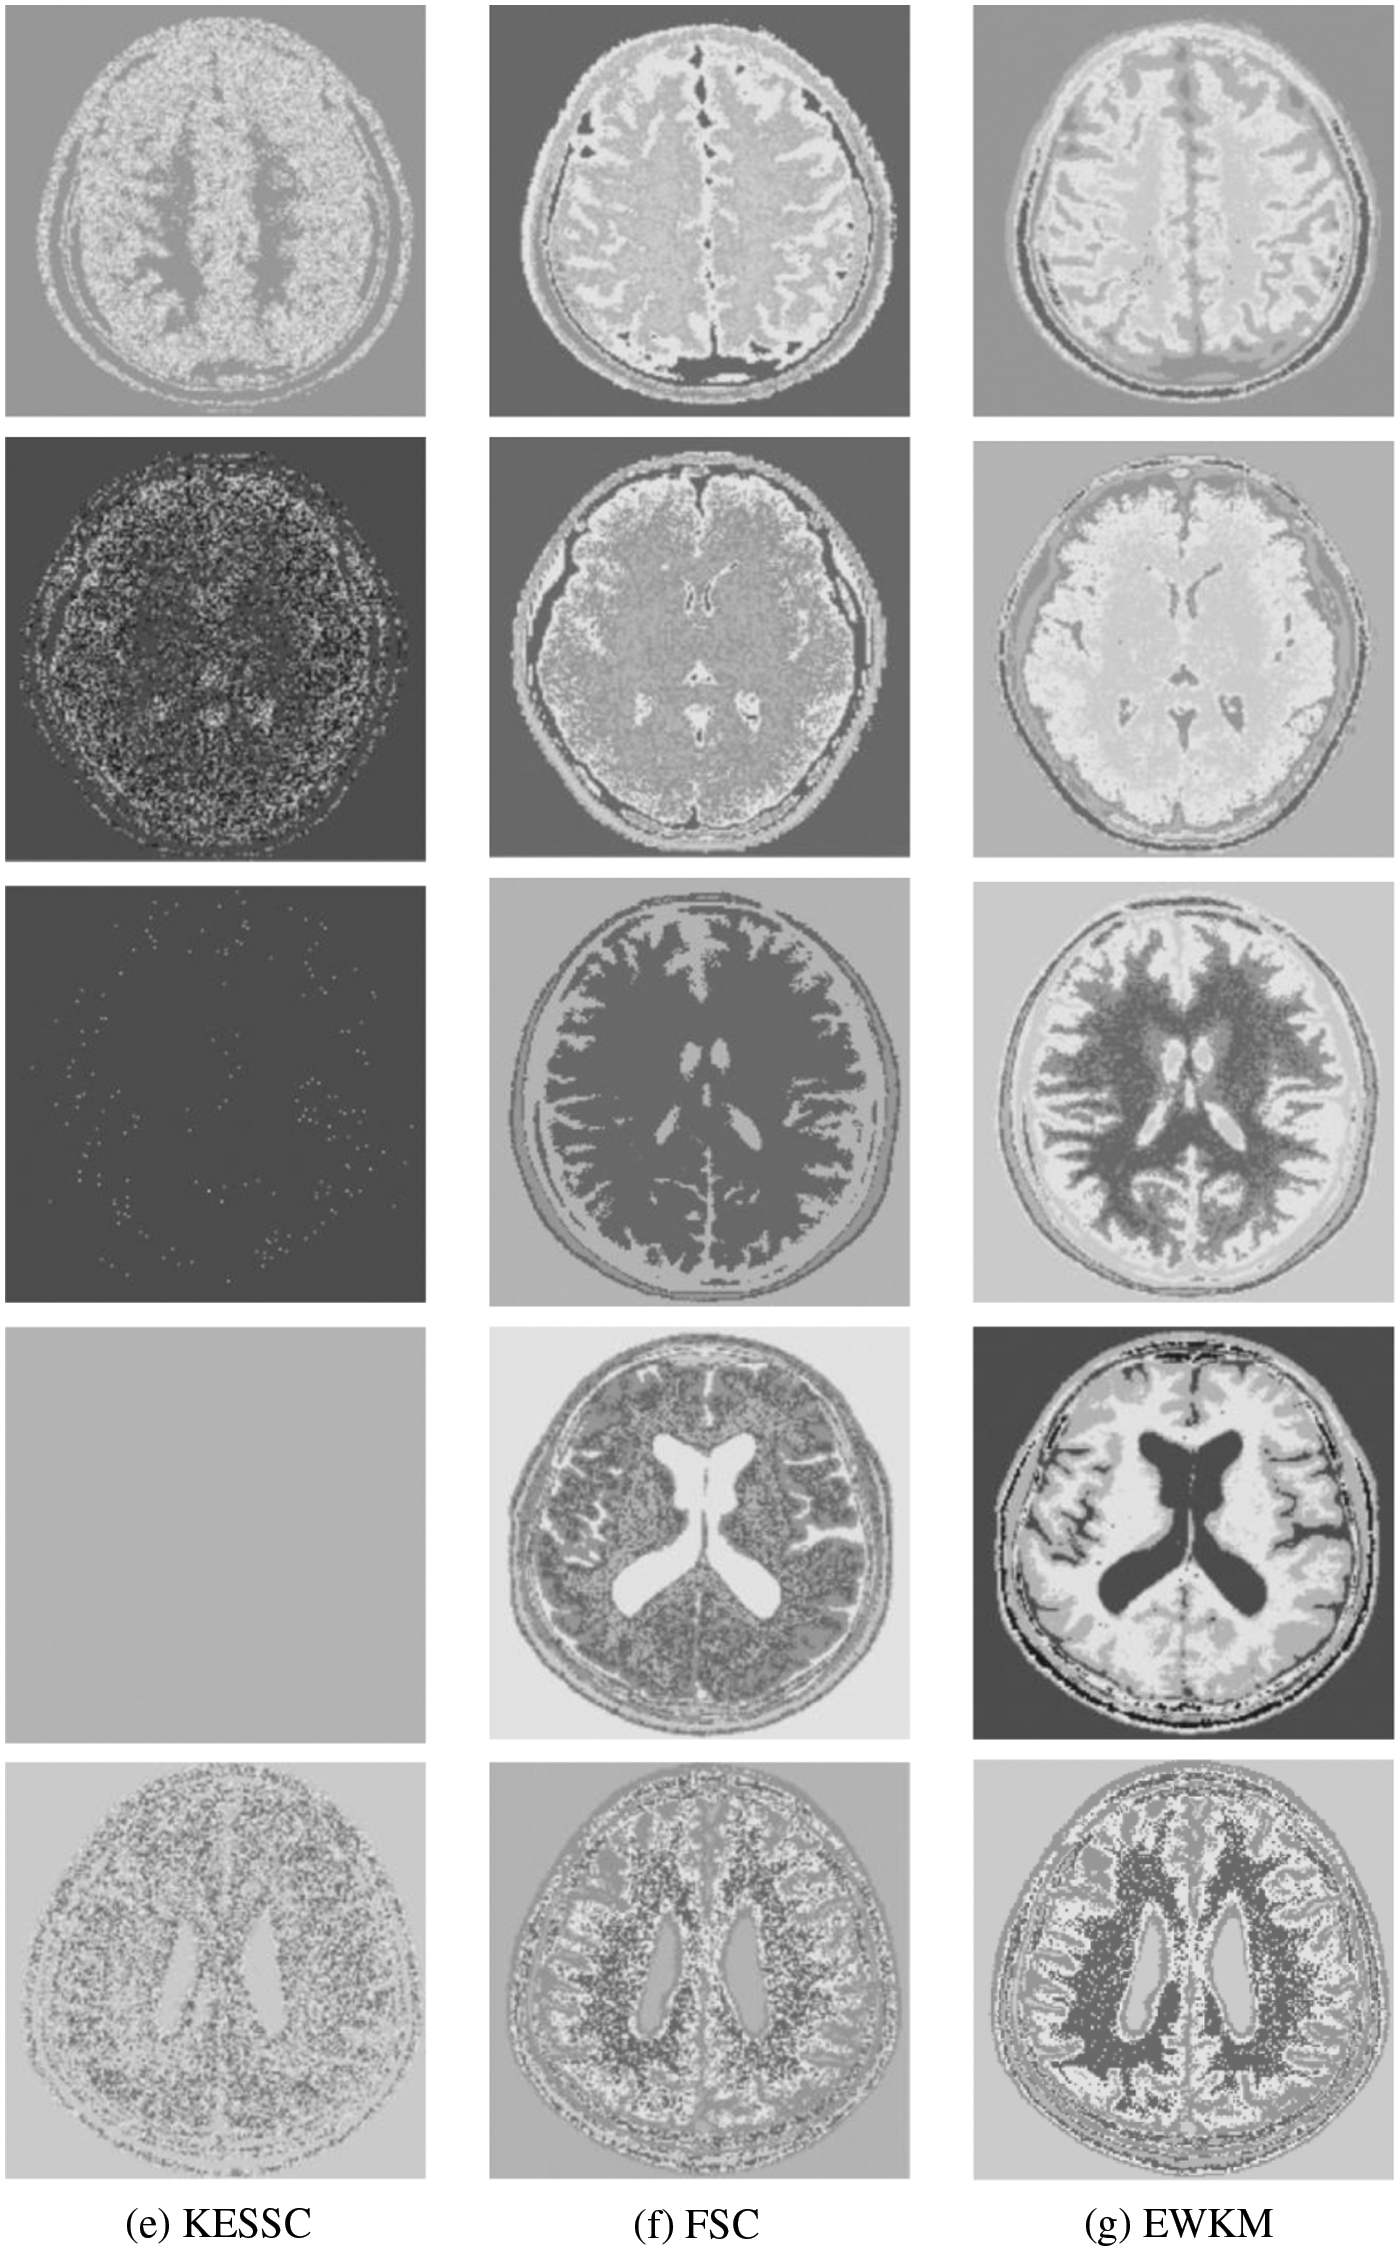

Because in the MR imaging process, the real and imaginary parts of the signal are disturbed by Gaussian noise with uncorrelated zero mean and the same variance at the same time due to the influence of environment and equipment, in order to verify the anti-noise property of GAESSCND, the noise addition process is performed again for the image to simulate the problems of blurred boundary and poor visual effect after the MR image is subjected to noise by adding speckle noise to the image provided by the hospital, taking the value of 0.03. By comparing the experiment with other soft subspace clustering, the segmentation effect obtained is shown in Fig. 5.

Figure 5: (a) Depicts the hospital brain MR image after noise, (b) is the segmentation effect of the proposed algorithm, (c) is the segmentation effect of the ESSCND algorithm, (d) is the segmentation effect of the ESSC algorithm, (e) is the segmentation effect of the KESSC algorithm, (f) is the segmentation effect of the FSC algorithm, and (g) is the segmentation effect of the EWKM algorithm

Through the experiments, (a) in Fig. 3 is the image after noise, and the (b–g) columns are all the effects after clustering segmentation of the brain MR containing noise. From a visual perspective, the GAESSCND algorithm has the strong anti-noise ability, among which KESSC has segmentation failure for serial numbers 3 and 4 and cannot segment the brain tissues in the images containing noise. Under the influence of noise, KESSC affects the weight allocation in nuclear space, most of which has zero weight. After the cluster center and membership fall into the local optimal solution in the iteration, the experimental results are wrong, and the brain tissue cannot be segmented from the image containing noise. KESSC is also more suitable for high-dimensional datasets and does not have a good processing advantage for noisy data. From the experimental data obtained in Table 4, it can be seen that GSESSCND shows very good results for all five noise-added brain MR images. The rest of the soft subspace clustering shows insufficient noise immunity for the images with noise, and the brain MR images are segmented incorrectly.

Finally, the GAESSCND algorithm showed good clustering results for both hospital-supplied MR images and noise-added images, reflecting the robustness and noise resistance of the algorithm. From some of the compared soft subspace clustering algorithms, the rest of the soft subspace clustering showed unclear boundary segmentation, high noise content, and unclear soft tissue segmentation.